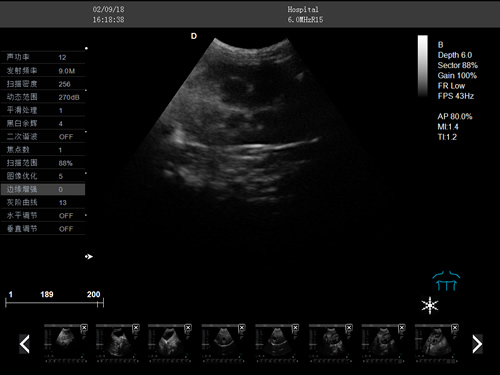

F3-VET推車式獸用彩超機

動物寵物超聲診斷儀

彩色多普勒動物超聲診斷儀

·中小動物的肝、膽,脾、腎、膀胱、子宮、妊娠等各組織器官的檢查和病變的診斷